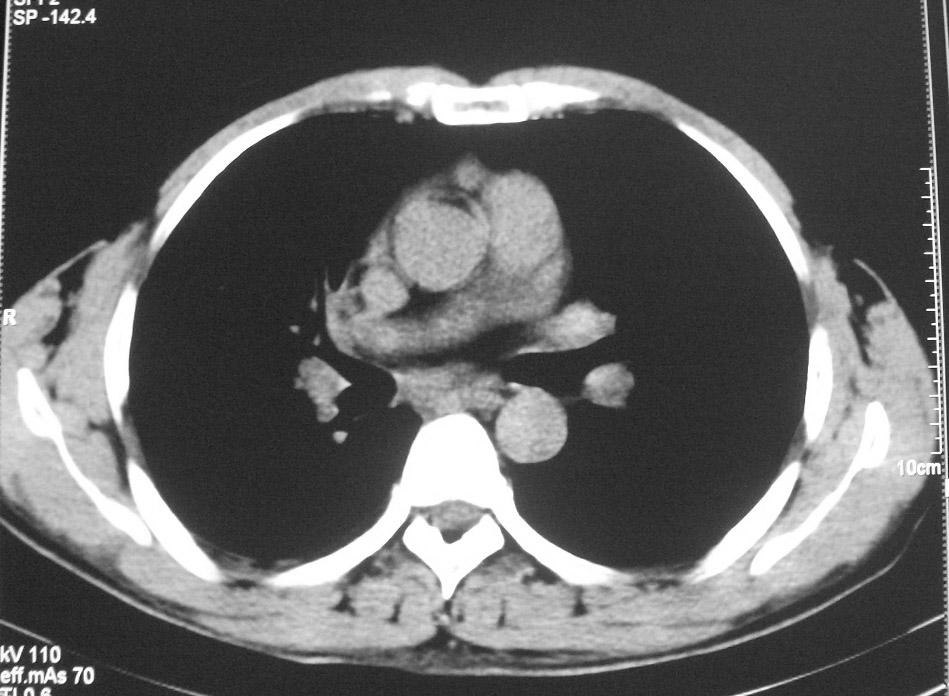

标题: CT5485:[原创]肺部占位请讨论

右上肺ca并肺不张,纵隔淋巴结转移

右肺上叶中央型肺癌并上叶肺不张、纵隔淋巴结肿大

右上叶支气管后壁明显增厚,支持右肺上叶中央型肺癌伴右上叶肺不张、纵隔淋巴结肿大。

考虑右上肺癌并肺不张,纵隔淋巴结转移

右上叶支气管后壁明显增厚,支持右肺上叶中央型肺癌伴右上叶肺不张、纵隔淋巴结肿大。建议支气管镜检查。

右上肺中央性肺癌伴右侧胸腔少量积液!右上肺胸膜下还有一小病灶,不完全排除结核,但个人支持恶性肿瘤!建议早穿刺活检。

右上叶支气管开口变窄,纵隔见肿大的淋巴结。支持右上叶中心型肺癌并右上叶不张纵隔淋巴结肿大。

右肺上叶中央型肺癌并上叶肺不张、纵隔淋巴结肿大.右侧少量胸腔积液。

右上肺中心型肺癌并肺不张,纵膈淋巴结肿大。右侧少量胸腔积液。

右肺上叶支气管后壁增厚,呈鼠尾状狭窄,纵隔内未见明显增大的淋巴结影,考虑为中央型肺癌伴右上肺不张